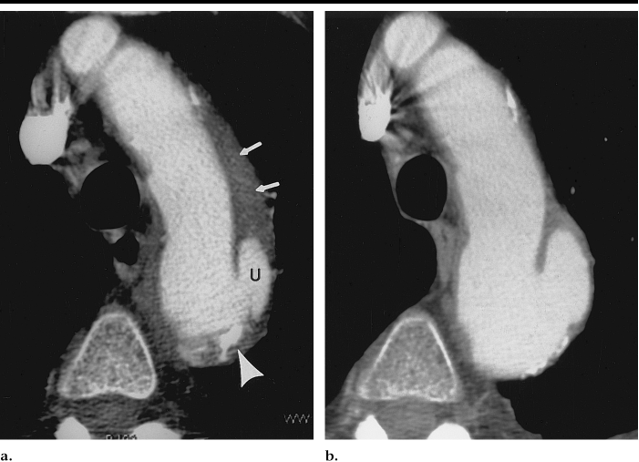

一线诊断手段:CT是PAU的一线诊断手段

大部分溃疡样主动脉病变保持不变随着时间的推移并且不会引起症状。大约三分之一的病变进展,通常导致伴轻度主动脉扩张,有时可能进展为囊状动脉瘤伴有主动脉扩张。对无症状的主动脉溃疡应行CT成像随访。

胸部主动脉PAU:有症状、或伴有壁间血肿等;无症状的PAU直径>2cm并且深度超过1cm。